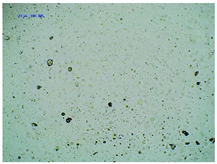

Some structural modifications of IBU dispersed in the adhesive matrix showed micrometric particle size which was recorded by microscopy. The observations were carried out on the day of receiving the patch, after 7 days simulating the conditions of the period of using the patch on the skin, and after 3 months, which was to reproduce the storage conditions of obtained patches in constant temperature (20 °C). Table 2 presents the crystallization of drugs quantitatively from the patch in the form of microscopic images, while Table 3 summarizes the sizes of the observed drug crystals. First, on receiving patches with new ibuprofen modifications, no significant differences in drug crystal sizes were observed compared to the reference patch containing unmodified ibuprofen (TP-IBU). The exception was the patch containing IBUNa which contained large drug crystals. This may be due to their poor solubility in solvents or the adhesive matrix in preparing adhesive compositions. After 7 days of observing patches not protected with siliconized foil, i.e., under conditions simulating their use, such as air access, small crystals are visible in all patches, regardless of the ibuprofen modification applied. Additionally, in this case, TP-IBUNa is distinguished by an increase in the size of the crystals during the seasoning. The final observation was on patches protected with siliconized foil, which were observed after 3 months. In this case, crystals of similar size were observed on the day of their preparation. Therefore, no drugs were synthesized from the patches, proving their stability during storage.

Microscopic observation of patch samples containing various structural modifications of ibuprofen during the seasoning time.

The size of drug crystals determined by microscopy.